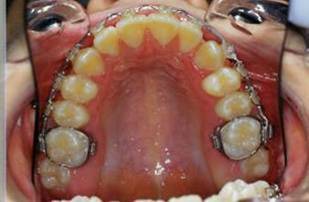

En fouillant dans mes cas j'ai trouve celui ci qui presente une beance assez importante. Je me suis rappele qu'un certain message etait lance il y a qq temps a propos d'un enfant qui presente une beance et de savoire comment faire dans ce cas. Je pense qu'il est interessant de voir comment les uns et les autres prennent en charge ce type de cas. Il s'agit d'un fille de 12 ans, succion de pouce, interposition linguale totale, beance de molaire a molaire, respiration mixte, incompetence labiale au repos, fonction labiale serree. Le total quoi!!! Voici la premiere serie de photos

4- Collage de l'arcade sup, presque 6 mois apres et voici le photo apres seance de college

Collage bas fait presque 3 mois apres le haut, avec des elastiques verticaux pendant 3 semaines seulement. Et voici les photos, la suite je vous en passe car il s'agit de simple finition.

P.S. photos au moment du collage bas